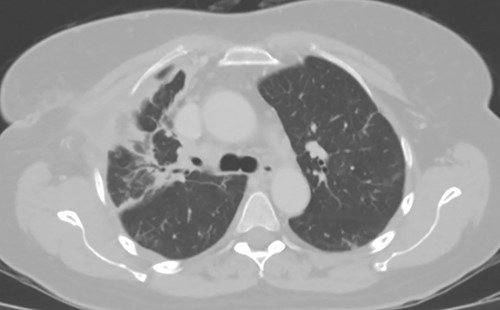

At the time of transfer, the patient was afebrile and hemodynamically normal, and she was not requiring supplemental oxygen. Her C-reactive protein level was 14.86 mg/l (reference <10) and white blood cell count was 8800 per mm3 (reference 4.5–10). Prior to transfer, her C-reactive protein level had been within normal limits. Computed tomography (CT) of the chest showed a residual pneumothorax (Fig. 2) and peripheral bronchopleural fistula (BPF). We treated her with open thoracostomy drainage (Clagett procedure), removing a segment of the second rib and suturing skin flaps to the thickened parietal pleura (Fig. 3). Due to institutional policy, no intra-operative images were obtained. On direct visualization, the visceral pleura overlying the upper lobe was thickened, but no frank purulence was noted. There was fibrinous exudate and air leak at two sites on the surface of the lung. A sample of the fibrinous tissue was sent to microbiology for clinical culture, which subsequently grew MSSA.

Axial image demonstrating right upper lobe consolidation and residual pneumothorax despite tube thoracostomy.